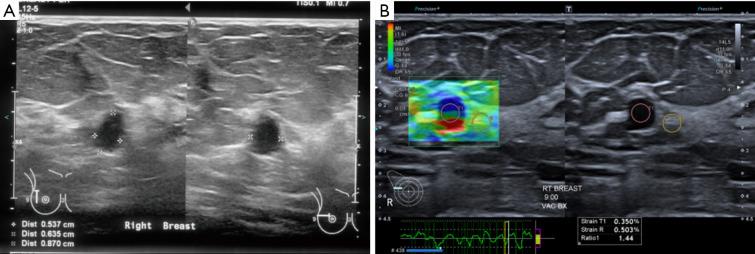

Several new ultrasound tools have been developed to further evaluate breast lesions detected on B-mode ultrasound. Strain elastography (SRE) was developed to assess the likelihood of malignancy of lesions based on their stiffness. This has been incorporated into the latest edition of the American College of Radiology (ACR) Breast Imaging Reporting and Data System (BI-RADS) lexicon and atlas. However, no agreed cut-off stiffness values have been established to distinguish benign from malignant lesions making the translation into routine clinical practice difficult. Superb microvascular imaging (SMI) was developed to better evaluate the vascularity within sonographic lesions and assess their likelihood of malignancy. However, there is also no agreed cut-off value for vascular index (VI) to distinguish between benign and malignant lesions. MicroPure was developed to better visualize and evaluate calcifications seen on ultrasound. Its effective use in breast screening and evaluating the calcifications detected for likelihood of malignancy have not been established. This article describes the original intended uses of these applications and reviews the studies evaluating them, showing the varying success of the translation of these tools into routine clinical practice. Also described are some other uses of these tools for which they were not originally intended. This illustrates the importance of being perceptive to alternative uses of imaging tools in their translation from bench to bedside.

已经开发了几种新的超声工具,以进一步评估在B型超声检查中发现的乳腺病变。应变弹性成像(SRE)是为了根据病变的硬度评估其恶性可能性而开发的。这已被纳入美国放射学会(ACR)乳腺影像报告和数据系统(BI-RADS)词汇表和图谱的最新版本。然而,尚未确定用于区分良性和恶性病变的一致的硬度临界值,这使得其难以转化为常规临床实践。超级微血管成像(SMI)是为了更好地评估超声病变内的血管情况并评估其恶性可能性而开发的。然而,对于区分良性和恶性病变的血管指数(VI)也没有一致的临界值。MicroPure是为了更好地显示和评估超声所见的钙化而开发的。其在乳腺筛查中的有效应用以及评估检测到的钙化的恶性可能性尚未得到证实。本文描述了这些应用的最初预期用途,并回顾了评估它们的研究,展示了这些工具转化为常规临床实践的不同成功程度。还描述了这些工具的一些并非最初预期的其他用途。这说明了在成像工具从实验室到临床的转化过程中,敏锐地感知其替代用途的重要性。